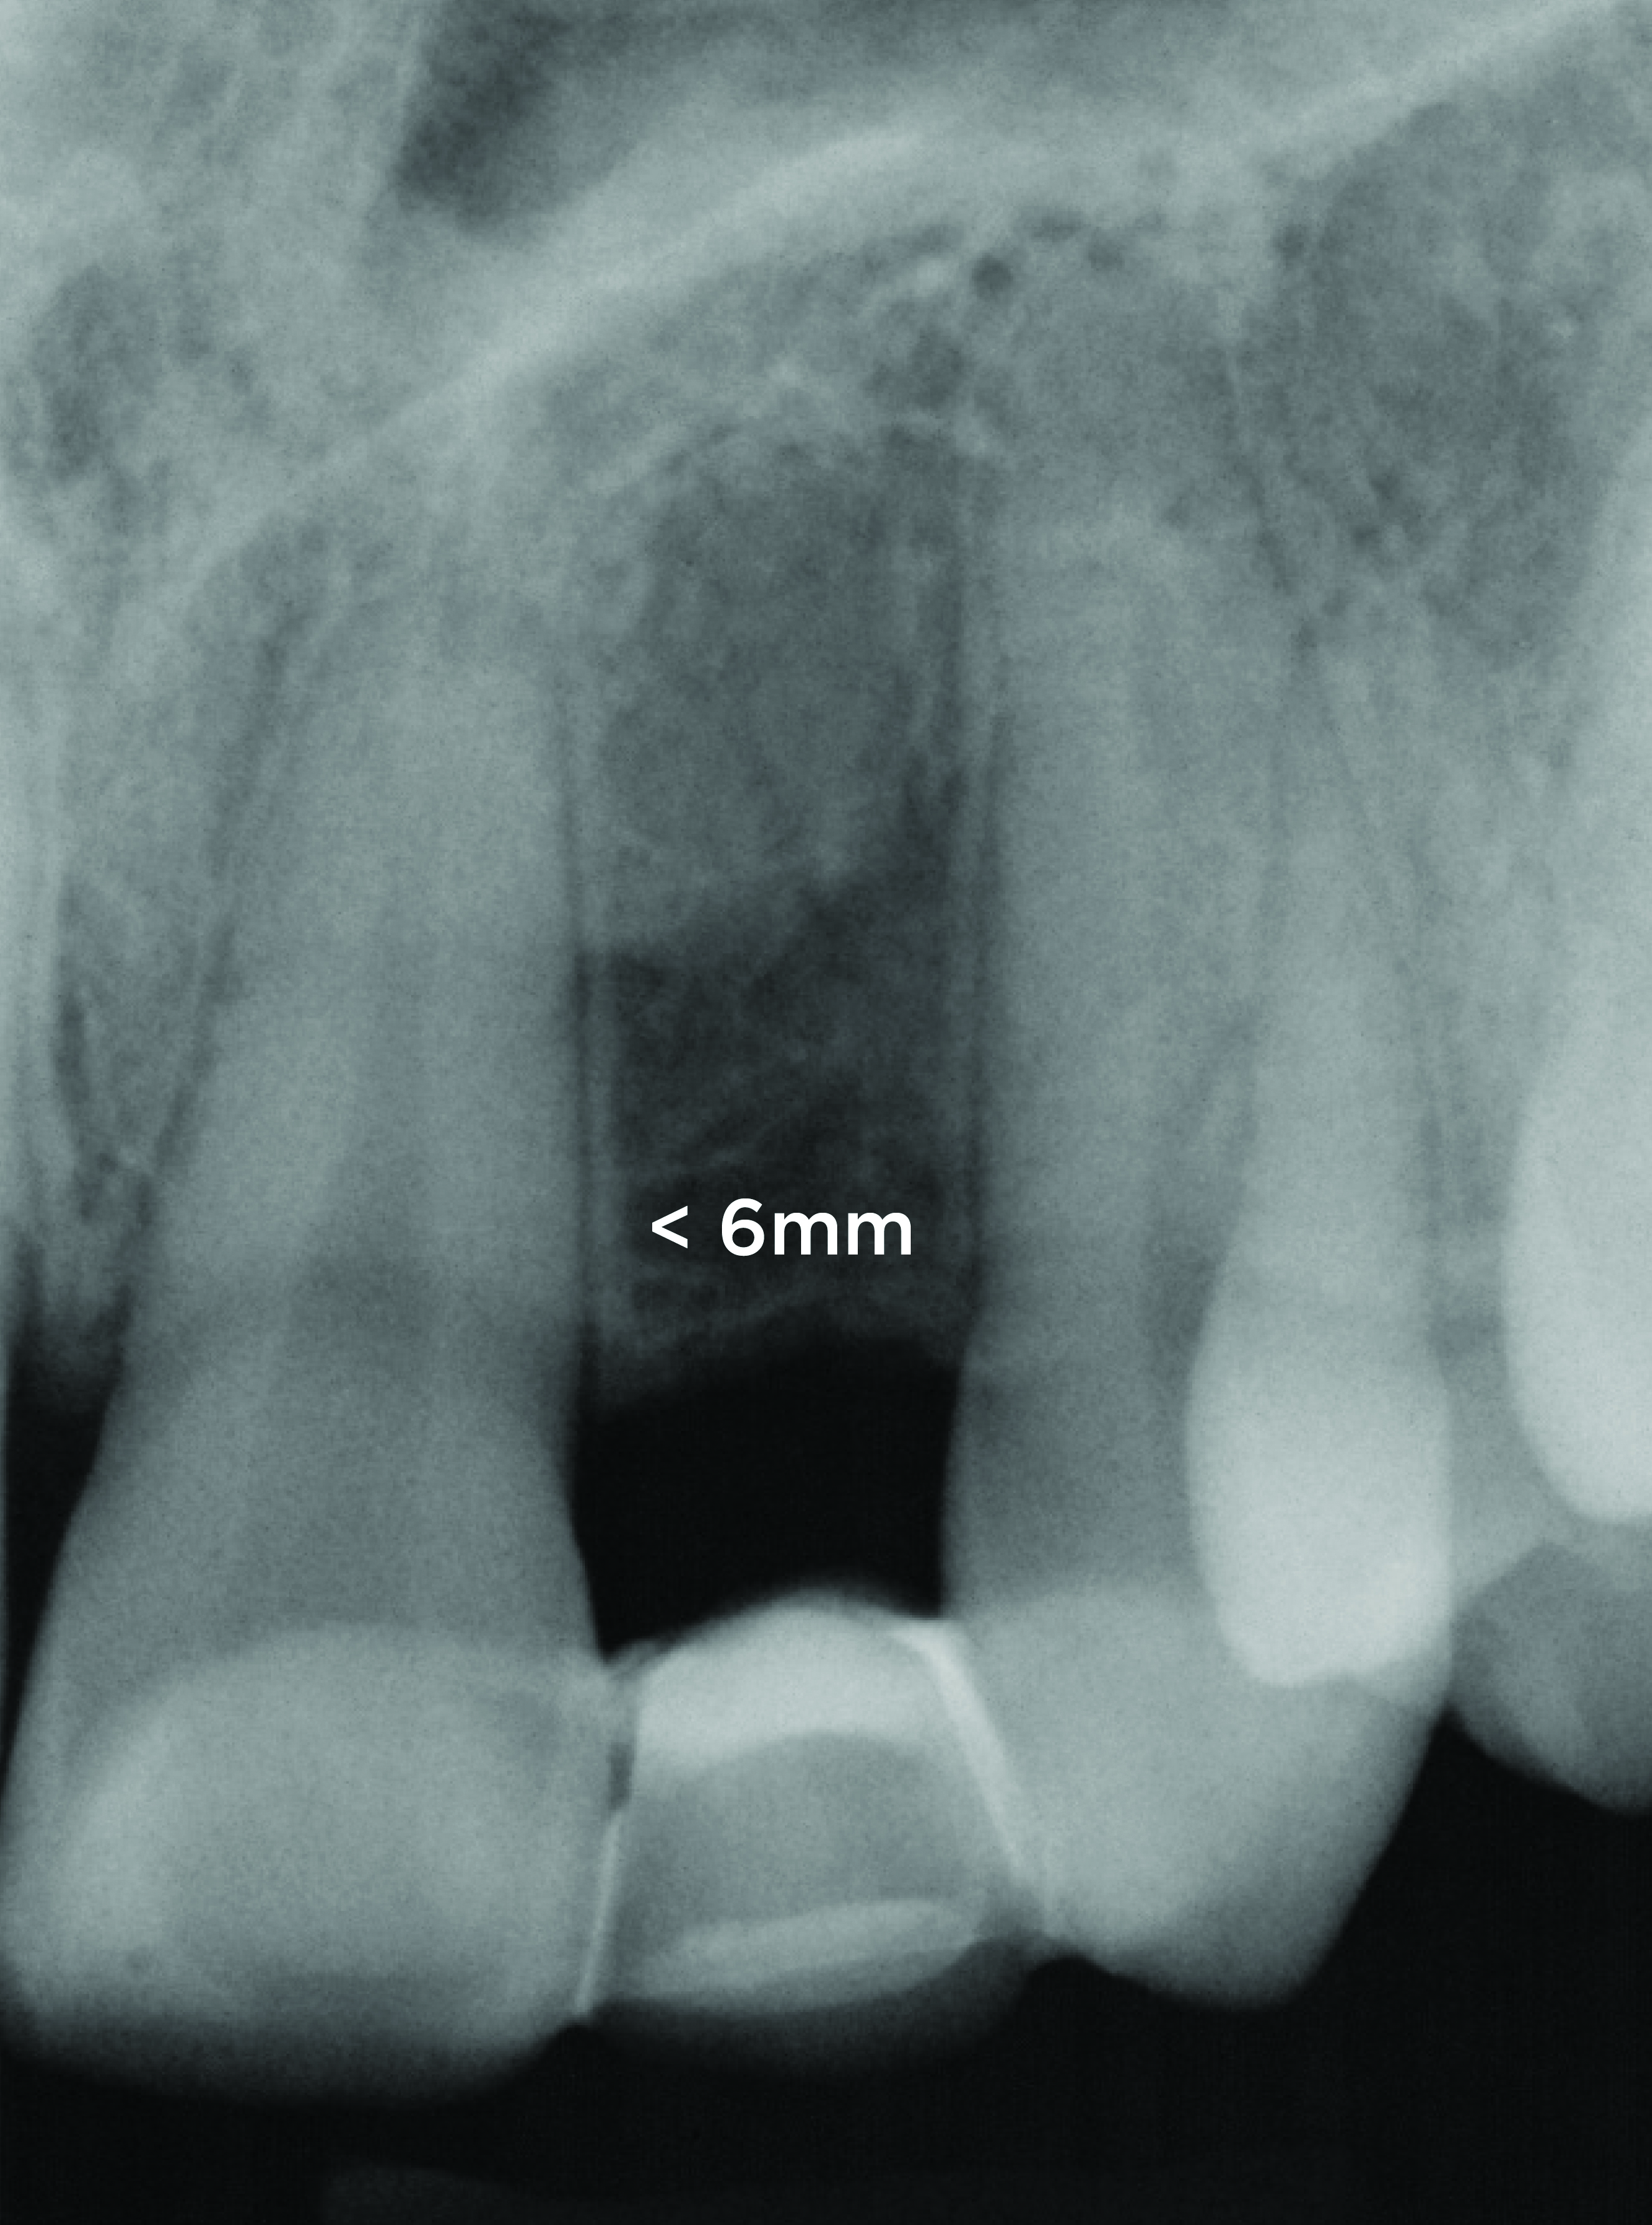

In the final case, adjacent implants were placed in healed sites No. 8 and No. 9 and provisionalized at the time of surgery (Figure 27 and Figure 28). This case illustrates the effect of platform switching on bone and gingival tissue stability, as well as recognizing that appropriate diameter and spacing is important to maintain ideal ridge contour. The gingival tissue anatomy between implants is characteristically shorter than papilla form between adjacent teeth, and, as a consequence, it is important to incorporate implant designs and procedures that minimize bone-level changes and associated soft-tissue recession. The depth of implant placement was subcrestal relative to the ridge crest, based on the future desired free gingival tissue level, while allowing prosthetic running room. The studies of Barros et al and Veis et al noted that implants positioned subcrestally (as seen in Figure 29) showed better crestal bone preservation than those placed equicrestally or supracrestally.28,29 The implant design used in this case achieves excellent primary stability. Along with the optimal 3-dimensional positioning of the implants and, specifically, the subcrestal placement, as well as the immediate provisionalization protocol, these concepts and implants have contributed to a pleasing esthetic outcome, as seen in Figure 30.

Fig 28. Radiograph on the day of surgery: Implant placement and provisional restoration. Note that the implants are subosseous, as their position is defined by the desired facial free gingival margin position.

Figure 28

Fig 29. One-year radiograph of the definitive restorations on the implants Nos. 8 and 9. Note the crestal bone stability compared to the radiograph taken on the day of surgery in Figure 28.

Figure 29